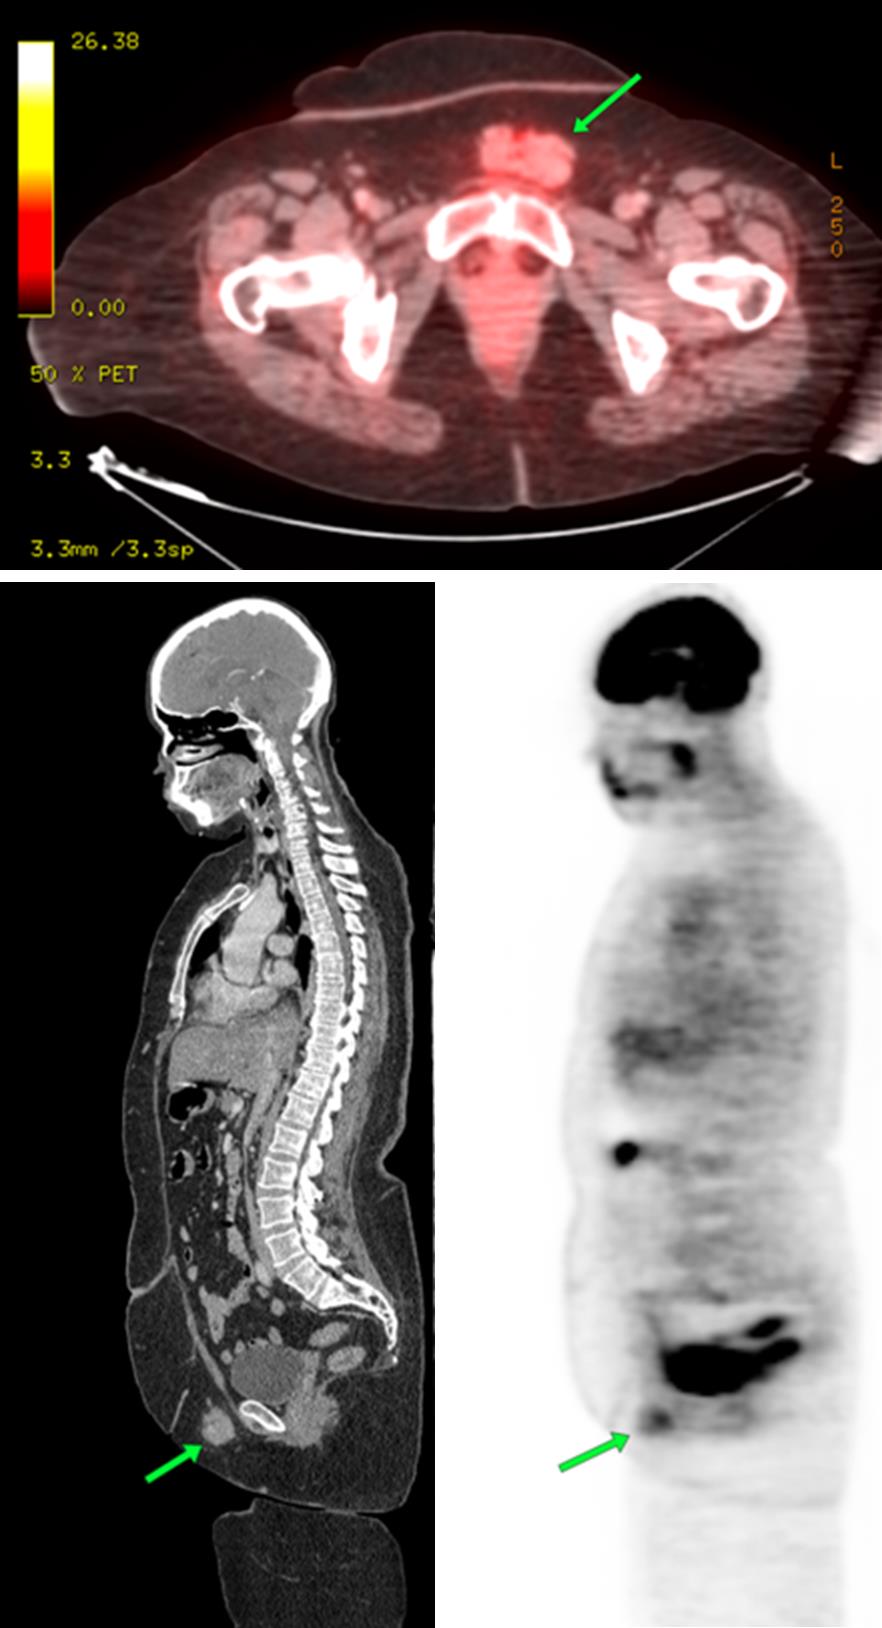

The most common cause of skin metastases in adult women is primary breast carcinoma, which comprises about 70% of cases [1]. Skin metastases have non-specific clinical appearances, making it challenging to differentiate them from other benign conditions [1]. We present a case of a 52-year-old female with type II diabetes and a three-month history of refractory skin lesions who did not respond to anti-inflammatory treatment. The patient subsequently complained of a right breast lump, evaluation of which led to the diagnosis of bilateral synchronous invasive lobular carcinoma.